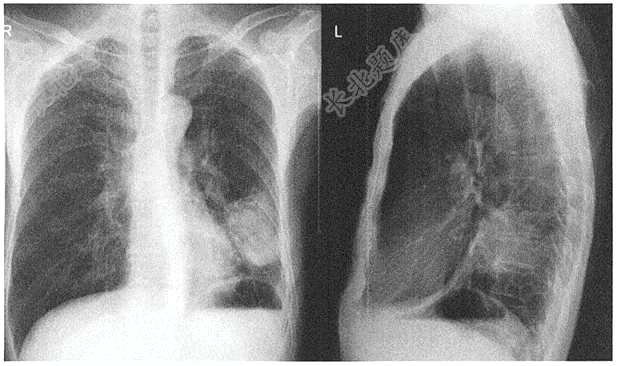

- 单项选择题中年男性患者,因咳嗽、咳痰、痰中带血一周入院,既往体健,有30余年吸烟史,吸烟≥400支/年。入院体查:左侧锁骨上可扪及肿大淋巴结,左下肺呼吸音稍低,无啰音。胸片如下图,请结合临床考虑患者最可能诊断是( )

A、浸润性肺结核

B、大叶性肺炎

C、中央型肺癌

D、周围型肺癌

E、肺真菌病